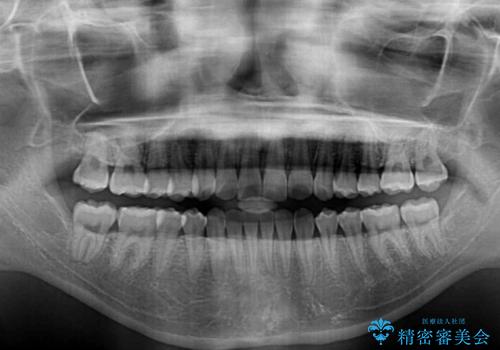

- 前に出ている上顎前歯が気になるとのことで来院された患者様です。

インビザラインを用い、IPR(歯と歯の間を削る)と歯列全体を後方に移動させることで、可能な限り前歯の突出感を改善することとしました。

元々の歯列も整っており、横顔の印象の出っ歯ではなかったため、仕上がりに満足できない可能性があると心配しておりましたが、口が閉じやすくなり、患者様には大変満足していただきました。